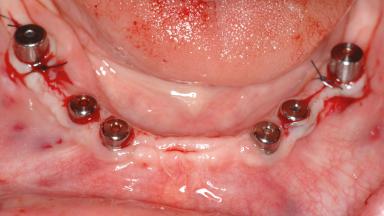

A 47-year-old woman who had suffered from aggressive periodontitis requiring a number of periodontal interventions over more than 10 years was referred by her general dental practitioner and periodontologist for bone augmentation and implant therapy. Her failing dentition had already been scheduled for extraction. The patient expressed a desire for implant-supported fixed restorations and esthetic improvement of her lower face. She had agreed to consult with a maxillofacial surgeon after the referring dentist had suggested bone augmentation. An initial examination by the maxillofacial surgeon revealed mobility of all residual teeth in a patient who was very unhappy with the function of her removable partial dentures. Due to periodontally migrated flaring teeth and loss of occlusal support, the vertical dimension of occlusion was dramatically reduced. The patient was displeased with her lower face because of deepened nasolabial, commissural, and supramental folds.